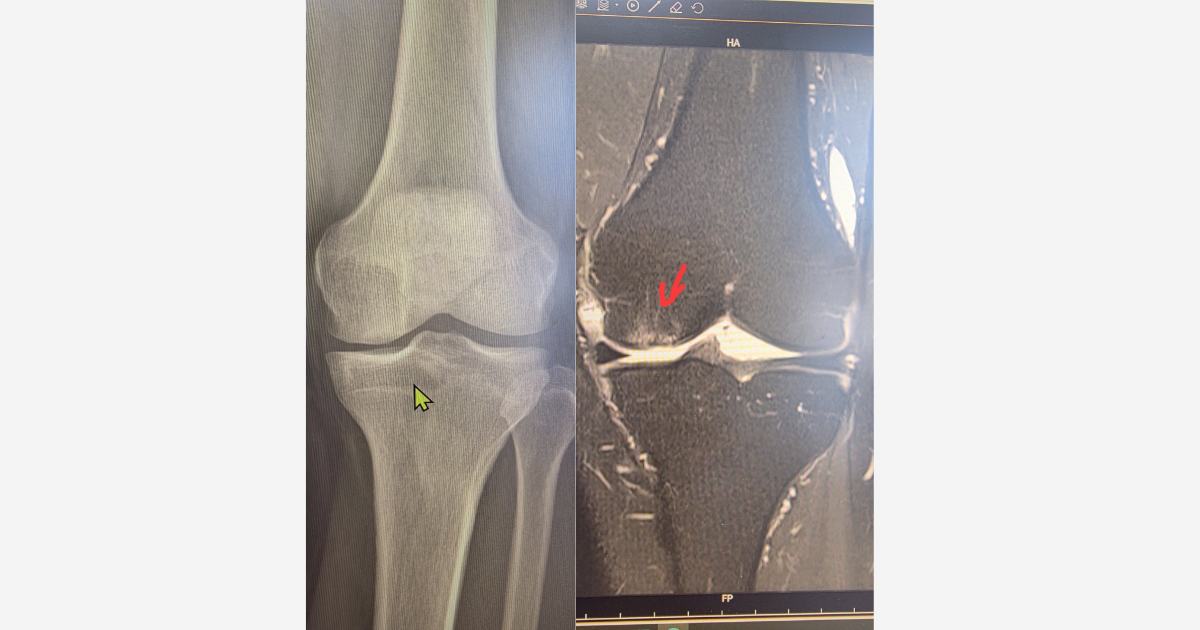

Tuần này, tôi gặp lại một bệnh nhân từng được ghép sụn khớp nhân tạo cách đây đúng 3 năm. Ca bệnh khi đó là tổn thương sụn khu trú vùng lồi cầu đùi trong, [...]